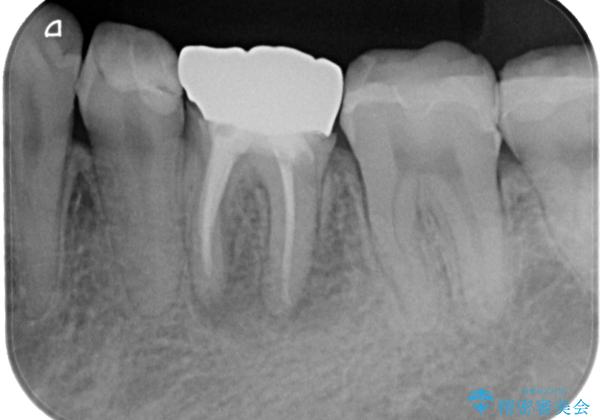

根管治療後は症状を確認し、速やかにオールセラミッククラウンにて補綴治療を行うこととしました。

病変が消退しているかどうか、半年、1年とレントゲン写真で経過観察を行う必要があります。

4ヶ月後のレントゲンでは、病変の消退が認められました。